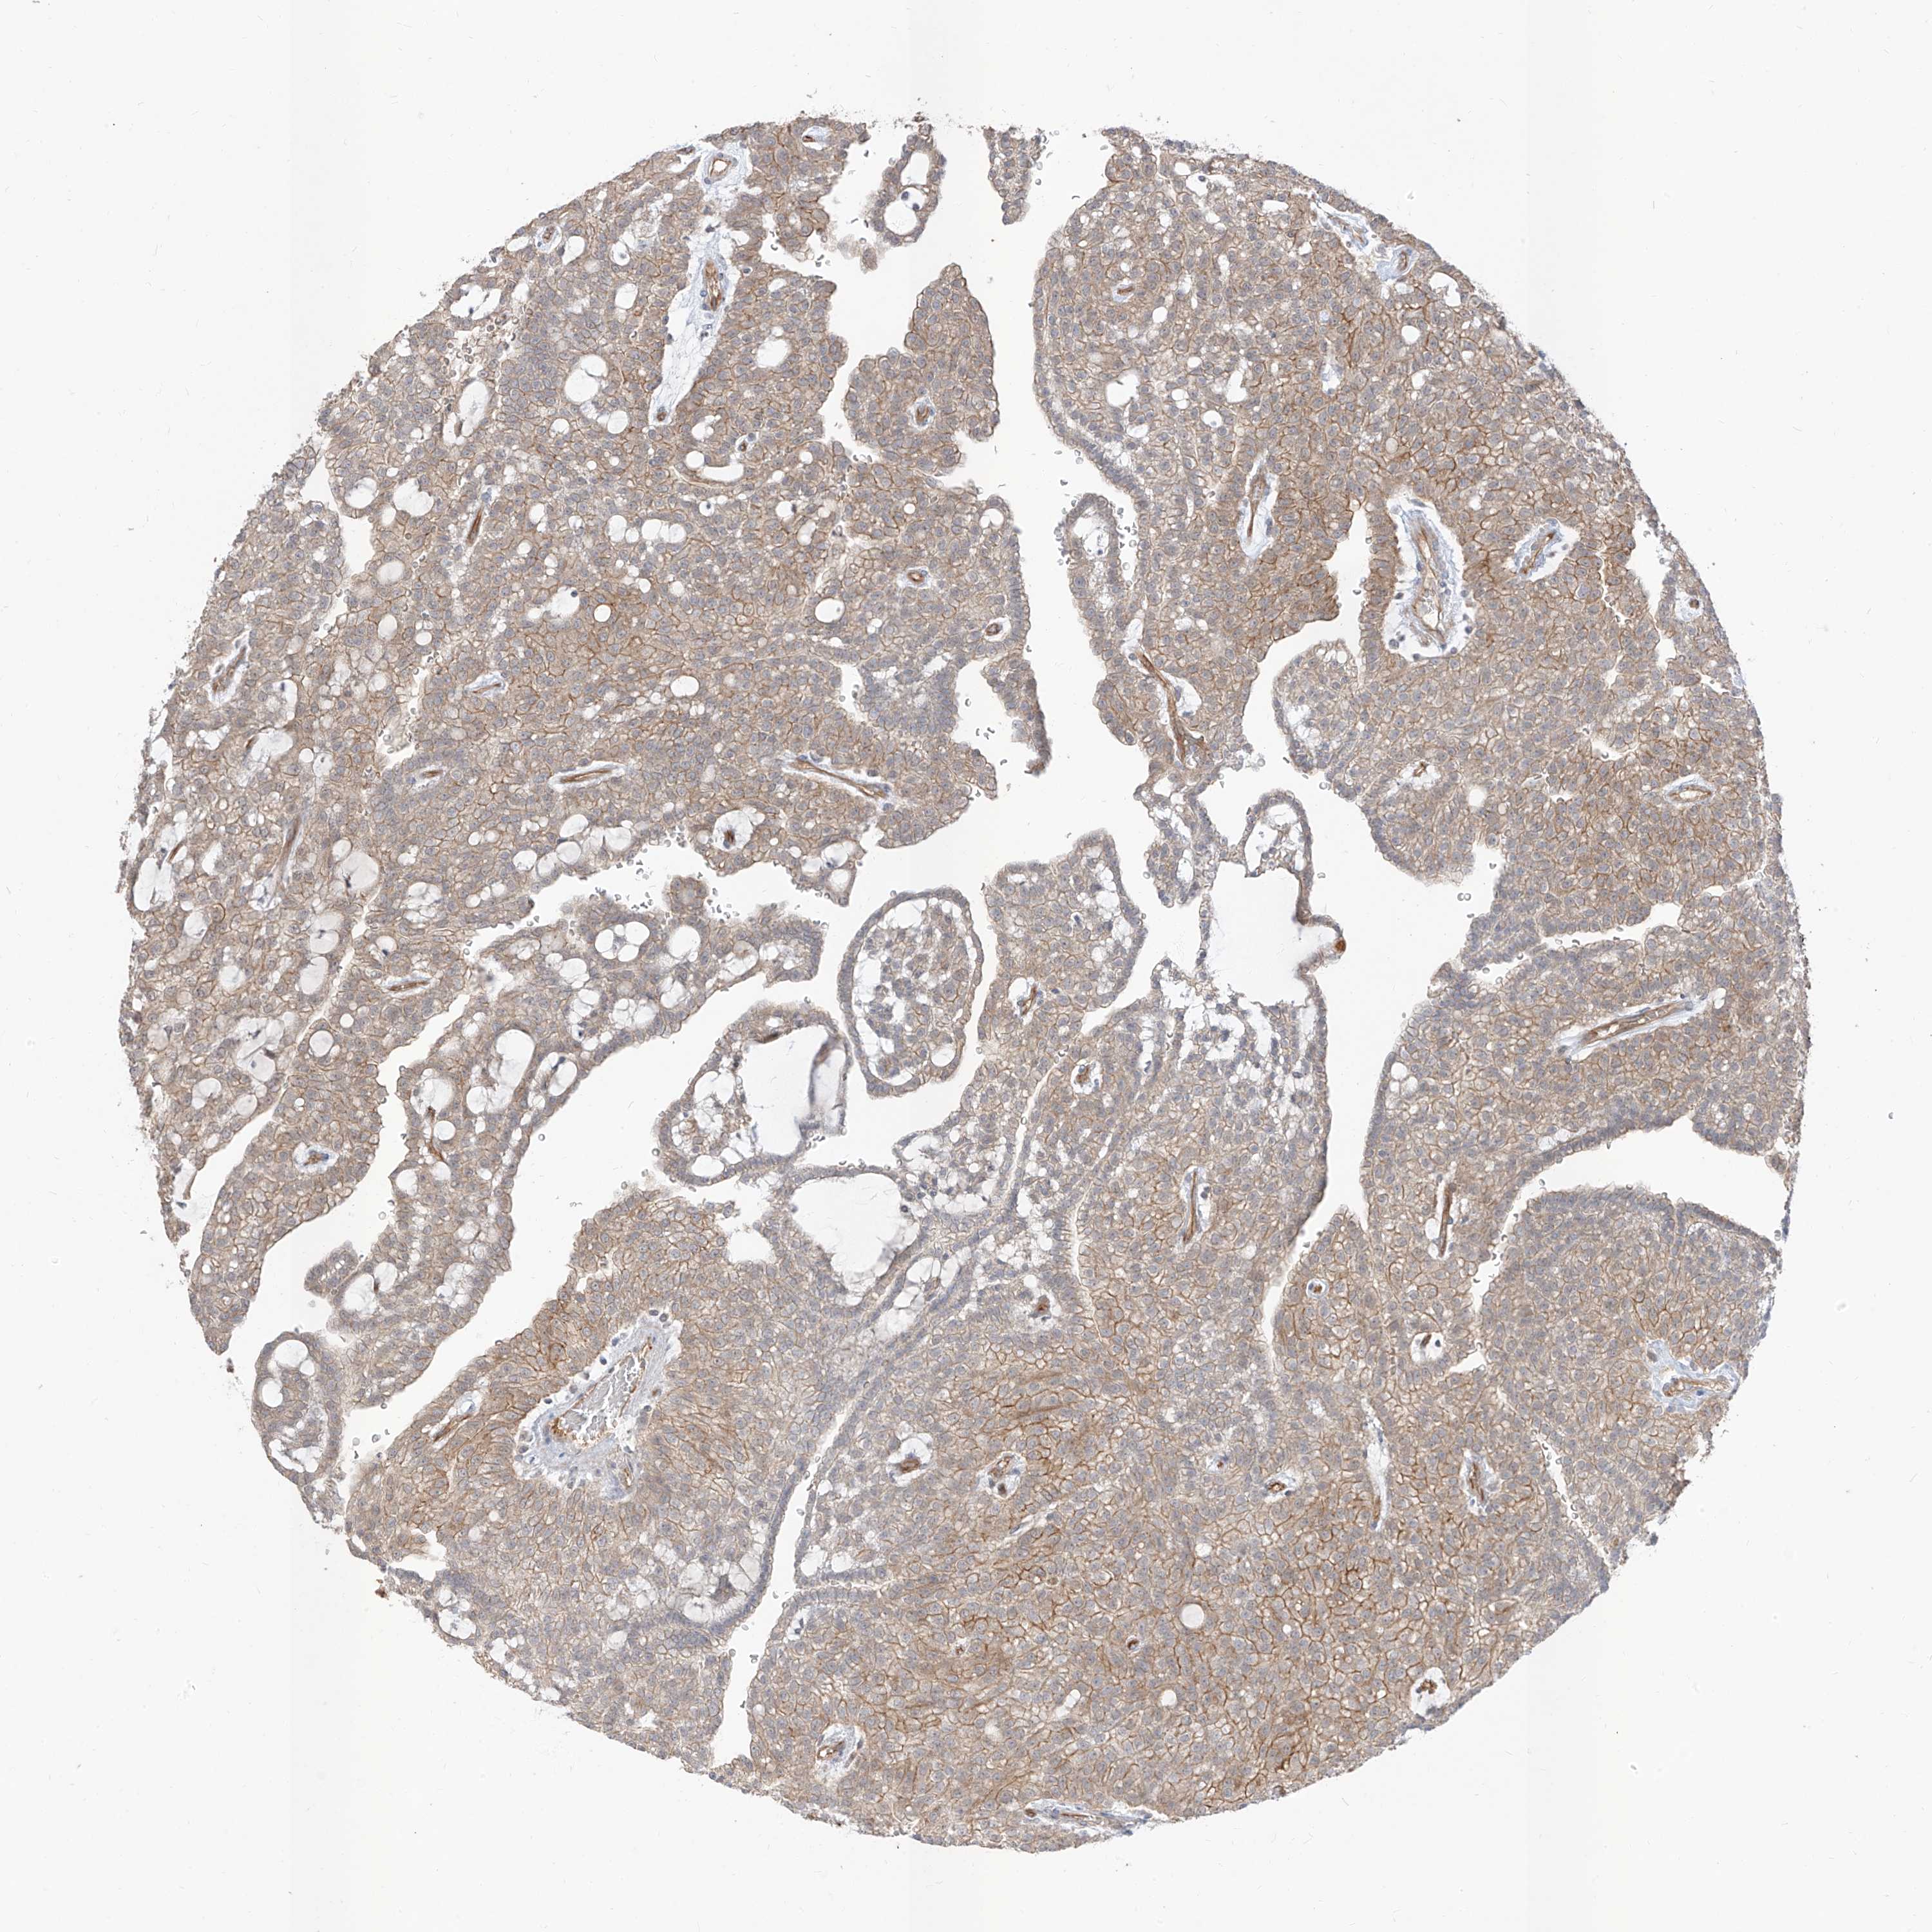

KIDNEY RENAL CLEAR CELL CARCINOMA (TCGA) - Interactive survival scatter ploti

The Survival Scatter plot shows the clinical status (i.e. dead or alive) for all individuals in the patient cohort, based on the same data that underlies the corresponding Kaplan-Meier plots. Patients that are alive at last time for follow-up are shown in blue and patients who have died during the study are shown in red.

The x-axis shows the expression levels (FPKM) of the investigated gene in the tumor tissue at the time of diagnosis. The y-axis shows the follow-up time after diagnosis (years). Both axes are complimented with kernel density curves demonstrating the data density over the axes. The top density plot shows the expression levels (FPKM) distribution among dead (red) and alive patients (blue). The right density plot shows the data density of the survived years of dead patients with high and low expression levels respectively, stratified using the cutoff indicated by the vertical dashed line through the Survival Scatter plot. This cutoff is automatically defined based on the FPKM cutoff that minimizes the p-score. The cutoff can be changed by dragging the vertical line or by entering a cutoff value in the square labeled "Current cut-off".

Under the Survival Scatter plot the p-score landscape (black curve; left axis) is shown together with dead median separation (red curve; right axis). Dead median separation is the difference in median mRNA expression between patients who have died with high and low expression, respectively. It is calculated as follows: median FPKM expression of dead patients with high expression - median FPKM expression of dead patients with low expression. This is intended to aid the user in visually exploring custom cutoffs and the associated p-scores and dead median separation.

Individual patient data is displayed and can be filtered by clicking on one or more of the category buttons on the top of the page. Categories describing expression level and patient information include: high, low, alive, dead, female, male and tumor stages. The scale of the x-axis can be toggled between linear and log-scale by clicking on the "x log" button. Mouse-over function shows TCGA ID, patient information and mRNA expression (FPKM) for each patient.

& Survival analysisi

Kaplan-Meier plots summarize results from analysis of correlation between mRNA expression level and patient survival. Patients were divided based on level of expression into one of the two groups "low" (under cut off) or "high" (over cut off). X-axis shows time for survival (years) and y-axis shows the probability of survival, where 1.0 corresponds to 100 percent.

EPHX4 is not prognostic in Kidney Renal Clear Cell Carcinoma (TCGA)

TCGA RNA samplesi

RNA-seq data is reported as average FPKM (number Fragments Per Kilobase of exon per Million reads), generated by the The Cancer Genome Atlas (TCGA) .

Normal distribution across the dataset is visualized with box plots, shown as median and 25th and 75th percentiles. Points are displayed as outliers if they are above or below 1.5 times the interquartile range. FPKM values of the individual samples are presented next to the box plot.

Average pTPM 1.4

Number of samples 521